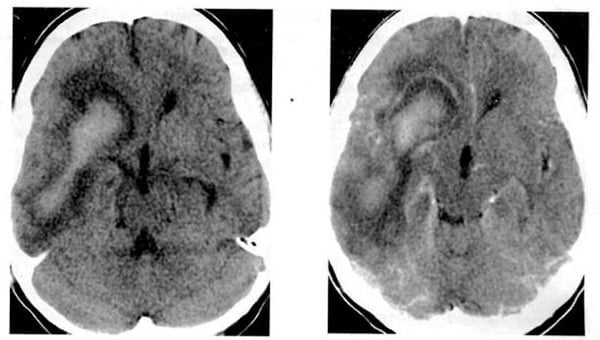

2.8. Máu tụ dưới màng cứng (Hình 1.43, 1.46-48)

Dấu hiệu XQCLĐT:

– Cấp. Khối tụ ngoài nhu mô, mật độ cao, hình liềm. Điển hình ở vùng trán-đỉnh, có thể lan vào khe liên bán cầu và dọc theo liềm đại não. Máu tụ dưới màng cứng nhỏ vùng dưới thái dương, dưới trán, lều, thấy rõ hơn trên lát cắt đứng ngang.

– Bán cấp (từ vài ngày đến 3 tuần). Mật độ ngang, làm di lệch mặt tiếp giáp chất xám-chất trắng. Sau tiêm, thấy các tĩnh mạch vỏ di lệch vào trong. Màng bên dưới có thể tăng quang.

– Mãn (trên 3 tuần). Khối tụ hình liềm, giới hạn rõ, mật độ thấp, tiếp giáp bản trong hộp sọ. Bắt chất cản quang viền mỏng.

Chú giải:

– Thường đi kèm tổn thương não bên dưới (dập, máu tụ cục bộ).

– Ở trẻ em, thường hai bên. Máu tụ dưới màng cứng liên bán cầu ở trẻ em và không có chỗ nào khác, phải nghi ngờ chấn thương không do tai nạn.

– Khi hiện diện cân xứng cả hai bên, đôi khi khó phát hiện nếu có mật độ ngang với vỏ não bên dưới. Tiêm chất cản quang để tìm những dấu hiệu gián tiếp.

– Xuất huyết tái phát trong khối tụ mãn dưới màng cứng có sẵn làm cho mật độ trở nên không đồng nhất.

Hình 1.46. Khối máu tụ dưới màng cứng hỗn hợp cấp và mãn trong khối tụ bên trái. Mật độ cao trong khối lớn mật độ thấp tương ứng máu tươi bên trong một khối tụ máu mật độ thấp mãn tính.

Hình 1.47. Khối máu tụ bán cấp dưới màng cứng có mật độ ngang. Trước tiêm, chỉ thấy hiệu ứng choán chỗ và xóa mất não thất bên bên trái (a). Sau tiêm (b), các tĩnh mạch bề mặt hiện lên (mũi tên) cho thấy rõ hơn ranh giới của khối tụ máu.

Hình 1.48. Máu tụ mãn dưới màng cứng. Khối tụ hình liềm, mật độ thấp (mũi tên) với bắt chất cản quang theo viền.